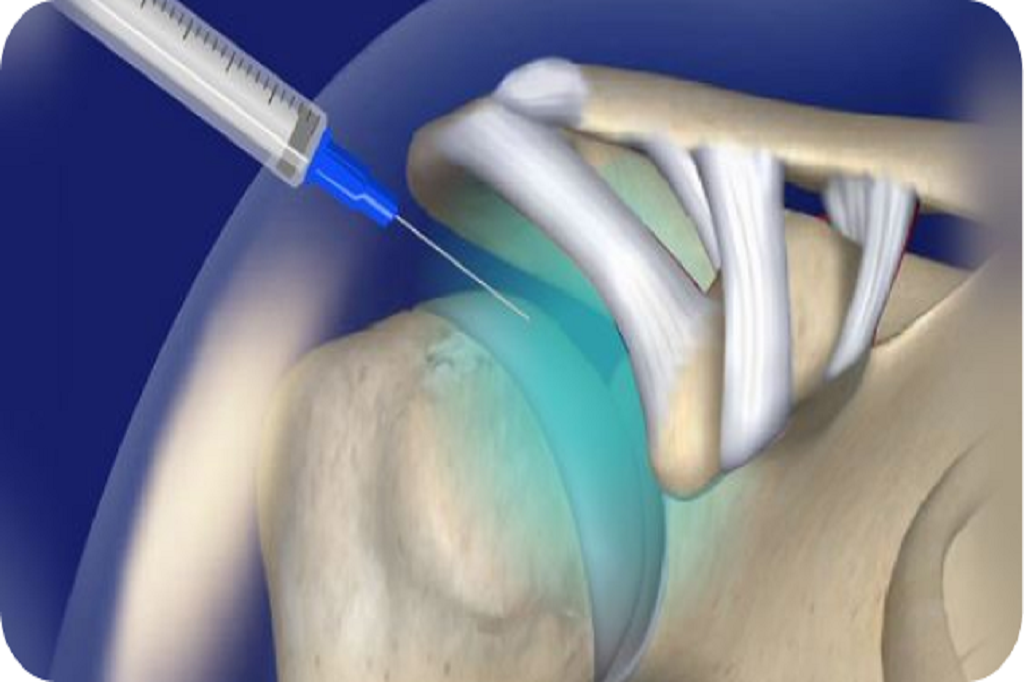

injections, including steroids for acute inflammation and advanced biologics like PRP, to reduce pain and improve mobility.